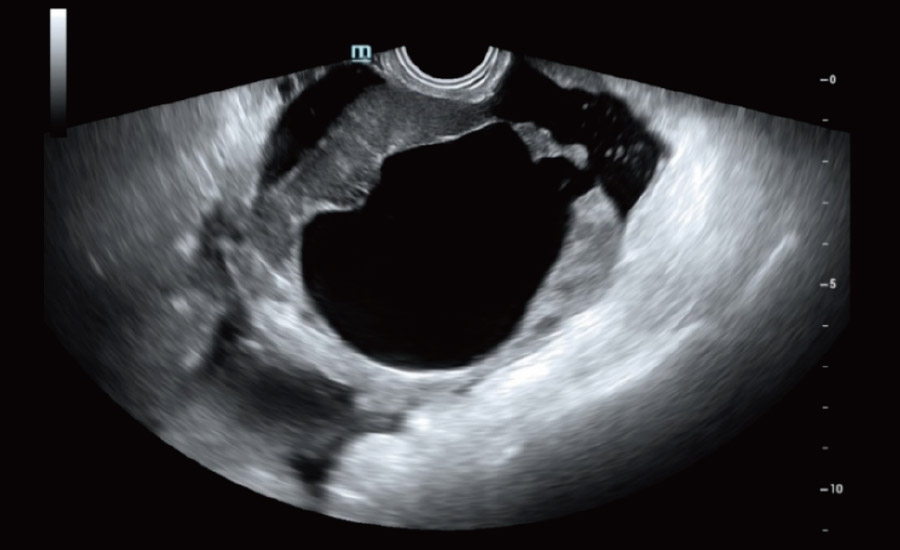

UMA (angiografia ultramicroscĆ³pica)

A tecnologia inovadora elimina as limita??es das tradicionais imagens com Doppler. Com resolu??o espacial e sensibilidade de fluxo ultra-altas, permite a detec??o de perfus?es de fluxos muito sutis e lentos, ampliando assim a aplica??o clĆnica da avalia??o qualitativa e quantitativa do ultrassom no cĆ©rebro fetal, rins, placentas, endomĆ©trios, ovĆ”rios etc.

UMA ā Fluxo uterino e endometrial